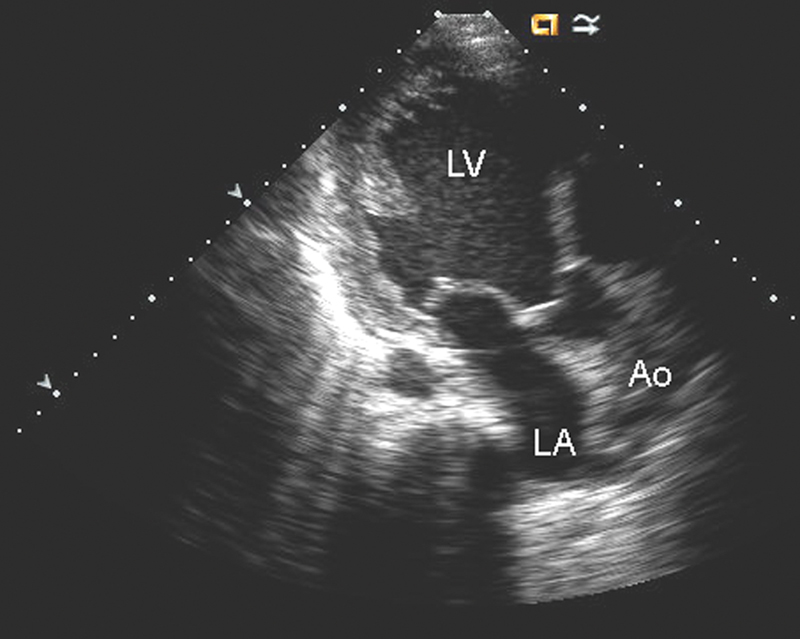

فحوصات تشخيصية لبعض امراض القلب والشرايين التاجية